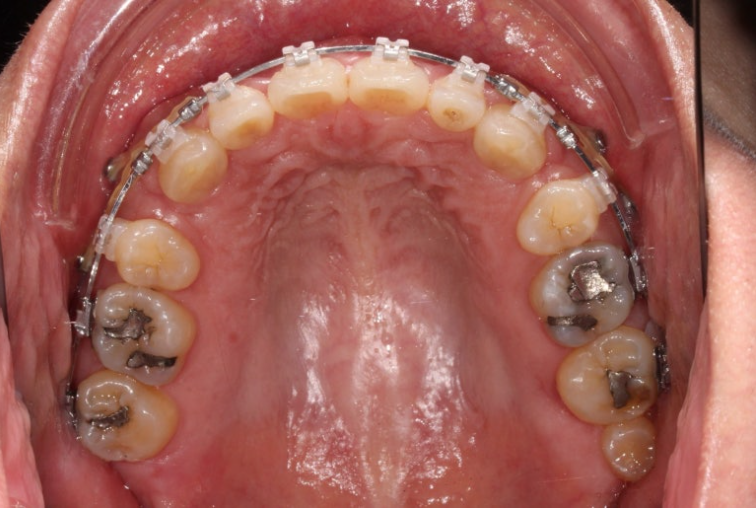

This patient was referred to us for orthodontic treatment three years ago.

You can see midline discrepancy and deep overbite.

The upper front teeth protrude forward.

According to the skeletal analysis, the patient has a recessed chin, meaning the lower jaw is smaller than the upper jaw.

The treatment plan was to extract only two upper premolars and use the wisdom tooth space in the lower jaw to move the teeth backward without extraction.

The patient chose Clippy-C, and treatment began.